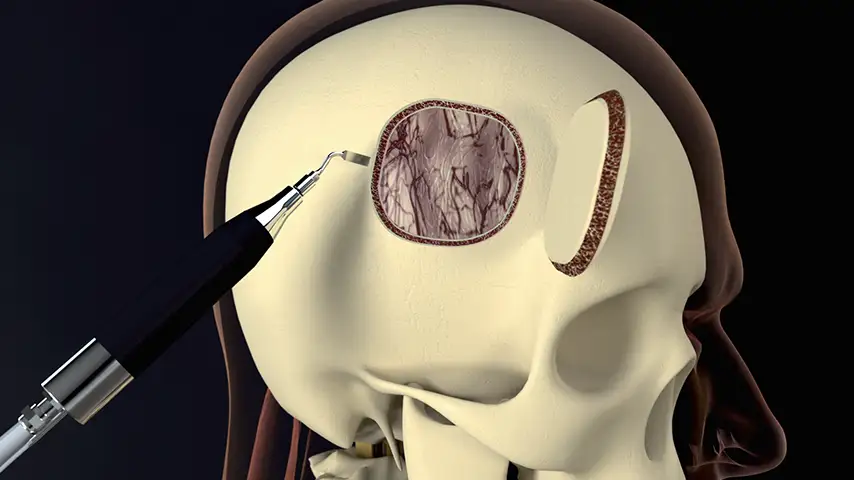

Craniotomy

and craniectomy

Advantages over traditional tools

Selective cut preserves soft tissue. (Dura, neves and vessels)

Exeptional precision and versatility in bone remodeling

Micrometric cut for minimal bone loss

Reduced need for fixation and graft materials